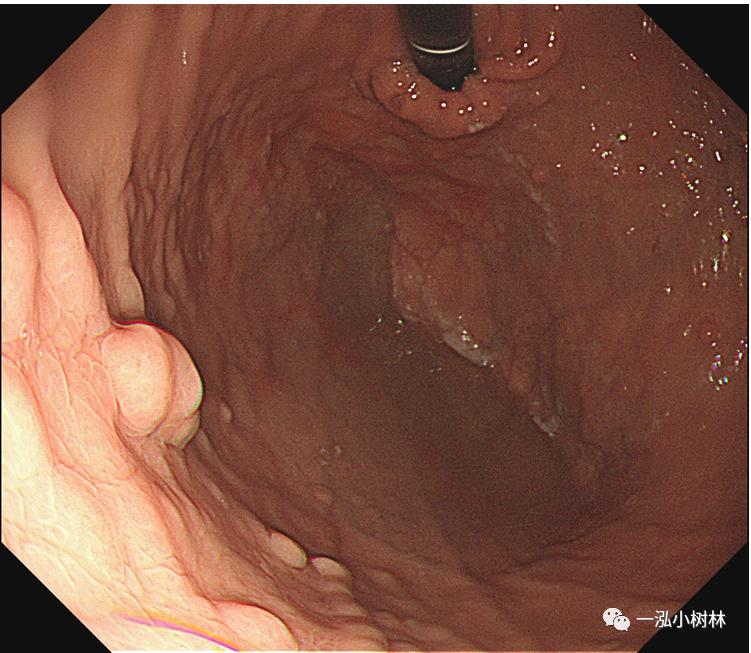

F 23,上腹部不适1年。

白光内镜:降部多发息肉

你想到的可能的诊断?